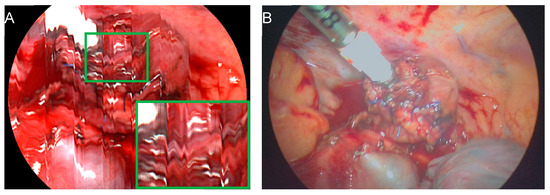

2.2. Surgical Procedure and Hyperspectral Imaging

- Köhler, H.; Jansen-Winkeln, B.; Maktabi, M.; Barberio, M.; Takoh, J.; Holfert, N.; Moulla, Y.; Niebisch, S.; Diana, M.; Neumuth, T.; et al. Evaluation of hyperspectral imaging (HSI) for the measurement of ischemic conditioning effects of the gastric conduit during esophagectomy. Surg. Endosc. 2019, 33, 3775–3782. [Google Scholar] [CrossRef]

- Thomaßen, M.T.; Köhler, H.; Pfahl, A.; Stelzner, S.; Mehdorn, M.; Thieme, R.; Jansen-Winkeln, B.; Gockel, I.; Chalopin, C.; Moulla, Y. In vivo evaluation of a hyperspectral imaging system for minimally invasive surgery (HSI-MIS). Surg. Endosc. 2023, 37, 3691–3700. [Google Scholar] [CrossRef] [PubMed]